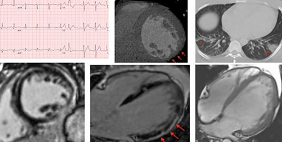

Among people hospitalized with COVID-19, preexisting heart disease nearly quadrupled their risk of acute events. |

Researchers have found circulating spike protein in the bodies of people with the complication, pointing to a potential mechanism. |

Top Stories in Cardiology: June 2020This month, Julia Grapsa and Mary Norine Walsh describe the many ways COVID-19 affects the heart. |